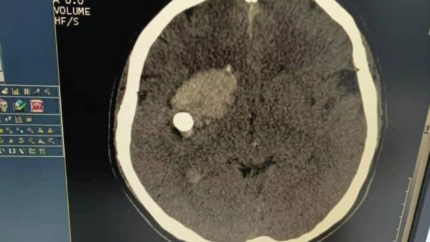

Кыргызстанские врачи спасли пациента с пулей в мозге

Врачи Кыргызстанской Республики успешно прооперировали пациента с пулей в голове.

Как сообщила пресс-служба Министерства здравоохранения, сложную операцию на мозге провели вчера в Джалал-Абадской областной больнице.

Пациента спасли заведующий нейрохирургическим отделением Абдибайит Идирисов и его команда. Сейчас состояние пострадавшего стабильное.

В Минздраве сообщили, что мужчина поступил с открытым пулевым ранением головы. Кто в него стрелял, пока неизвестно.